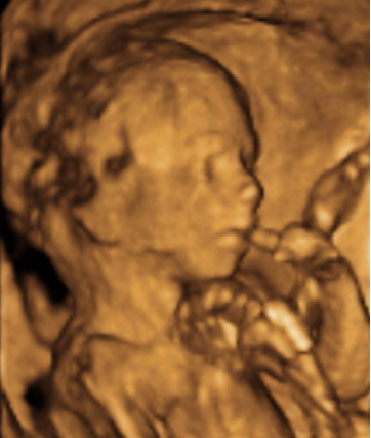

Ecografía: El bebé levanta los brazos

La ecografía capta al feto de 20 semanas de gestación en pleno movimiento ascendente.